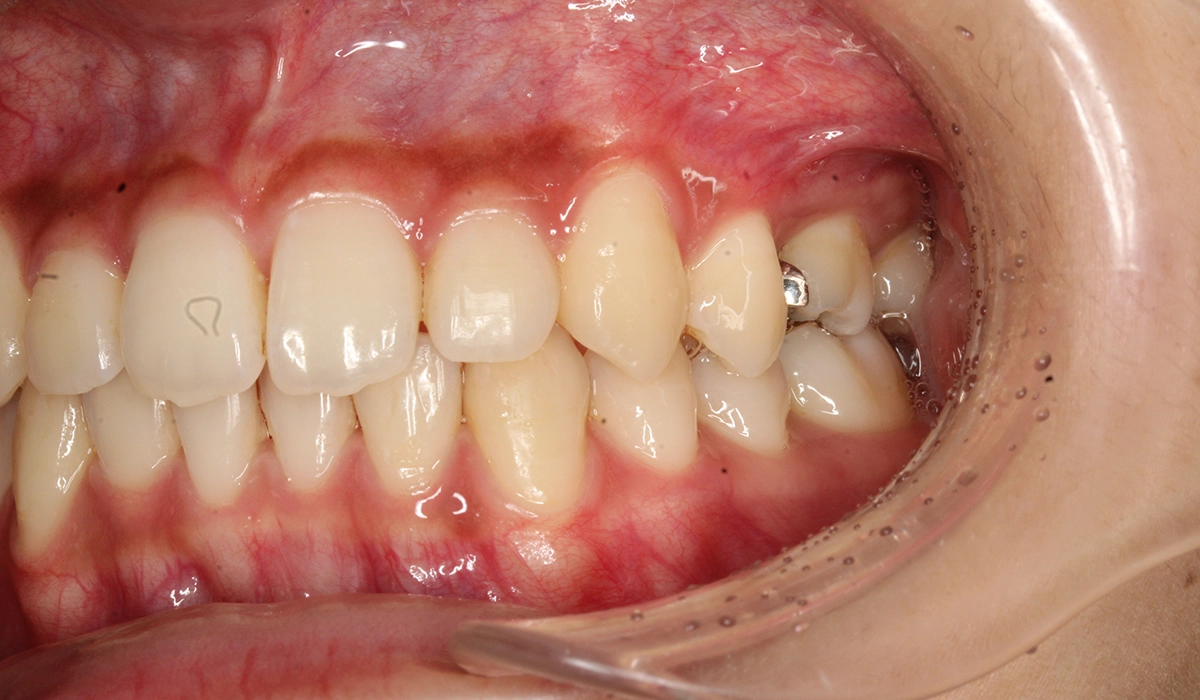

術前:右側

術後:右側